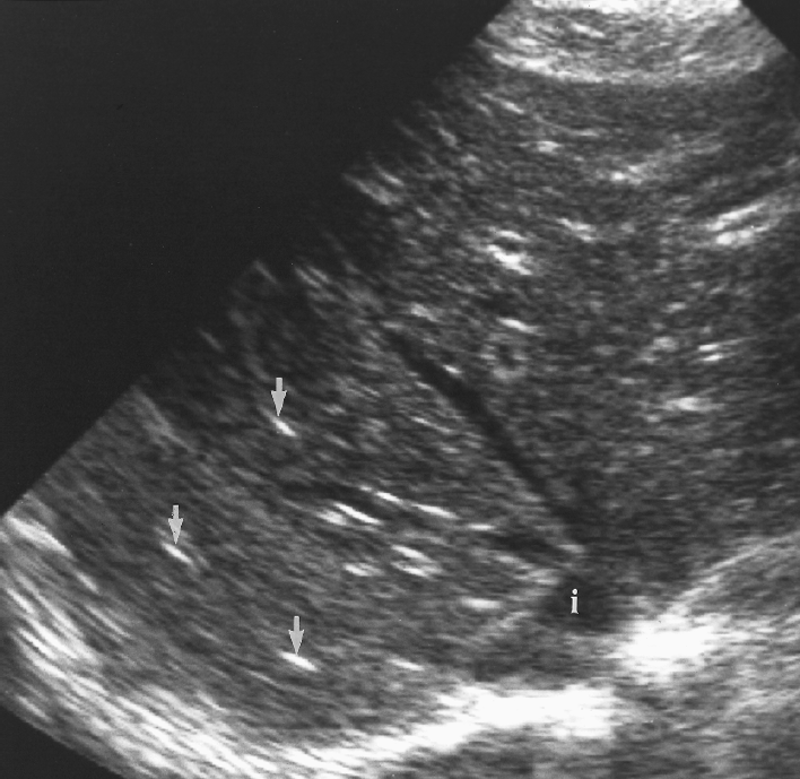

Explain the procedure of a liver exam.

Begin doing a full sweep through the liver. Starting sagittal,

slightly to the left of midline. Change to a transverse view and sweep

up and down the left lobe from a subcostal approach. Look in

transverse through the right lobe subcostally or

intercostally.

Explain the Sagittal plane for the liver exam.

The transducer may be swept under the intercostal margin to image the liver parenchyma from the anterior abdominal wall to the diaphragm.

Explain the Transverse plane for the liver exam.

The transducer should be angled in a steep cephalic direction to be as parallel to the diaphragm as possible. The transverse plan allows images of liver parenchyma, vascularity and ductal structures.

What are the Techniques used for the liver exam?

Deep inspiration and held.

Push belly out.

Alternate positions can be used to displace the bowel out of the field of view.

Place right arm above head to open intercostal spaces